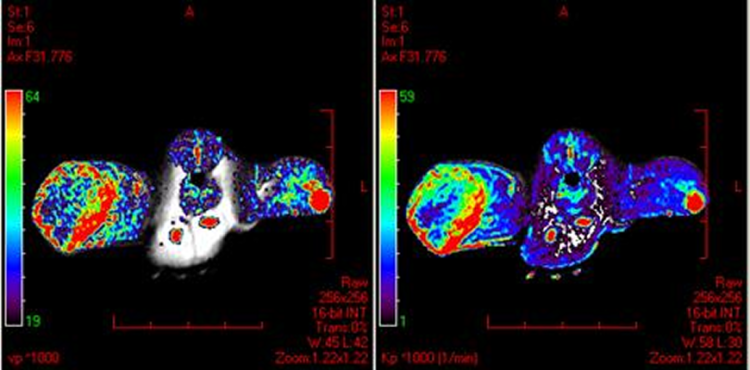

DCE-MRI with a new macromolecular contrast agent in a rat colorectal cancer model. Data courtesy of Drs Wim Ceelen and Peter Smeets, Gent University Hospital, Belgium.